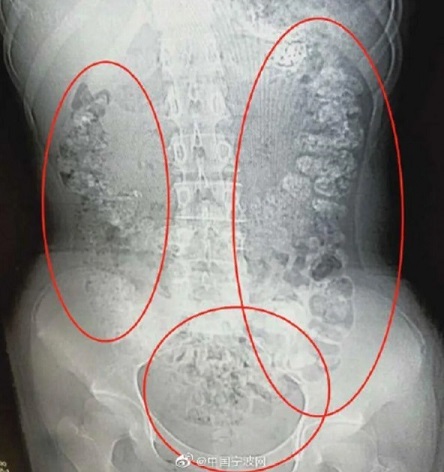

มีข้อมูลเท็จเกี่ยวกับชานมไข่มุกเผยแพร่ทางสื่อสังคมออนไลน์ในต่างประเทศ โดยอ้างว่าการดื่มชานมไข่มุกต่อเนื่องมีความอันตราย เพราะรายงานข่าวปี 2019 พบเด็กหญิงวัย 14 ปีในมณฑลเจ้อเจียง สาธารณรัฐประชาชนจีน ป่วยด้วยอาการท้องผูกและกินอาหารไม่ได้ เมื่อแพทย์ทำการตรวจสอบด้วยวิธี CT Scan พบวัตถุลักษณะคล้ายไข่มุกที่ยังไม่ถูกย่อยจำนวนมากอยู่ในระบบทางเดินอาหาร เชื่อว่าเกิดการจากการดื่มชานมไข่มุกมากเกินไป

อย่างไรก็ดี รายงานข่าวชิ้นนี้สร้างข้อสงสัยในวงการแพทย์ เพราะตามปกติแล้ว การ X-Ray จะไม่แสดงภาพอาหารในระบบทางเดินอาหาร

ดร.ลินา ฟิลิเปซ ผู้เชี่ยวชาญด้านกุมารเวชศาสตร์โรคระบบทางเดินอาหารและโรคตับ โรงพยาบาล Nicklaus Children’s Hospital ในเมืองไมอามี สหรัฐอเมริกา ชี้แจงต่อเว็บไซต์ Live Science ว่า ไม่ใช่เรื่องแปลกที่การบริโภคไข่มุกจากชานมไข่มุกมากเกินไปจะทำให้ท้องผูก แต่ความผิดปกติของเคสนี้คือการเห็นไข่มุกจำนวนมากในภาพ X-Ray

เนื่องจากไข่มุกหรือสารเพิ่มความหนืดที่อยู่ในไข่มุกไม่จัดเป็นสารทึบรังสี (Radiopaque) และจะปล่อยให้รังสีเอ็กซ์ทะลุผ่านไปได้ ทำให้มองไม่เห็นในภาพ X-Ray

ดร.วลาดิเมียร์ คูชเนียร์ รองศาสตราจารย์คณะแพทยศาสตร์ มหาวิทยาลัยวอชิงตัน และโฆษกสมาคมแพทย์ระบบทางเดินอาหารประเทศสหรัฐอเมริกา ให้มุมมองที่คล้ายกันว่า หากภาพ X-Ray คือไข่มุกจากชานมไข่มุกจริง ๆ อาจเป็นไปได้ว่าไข่มุกดังกล่าวมีการใส่สารเติมแต่งที่ร่างกายไม่สามารถย่อยได้ ซึ่งอาจไม่พบในชานมไข่มุกทั่วไปในท้องตลาด